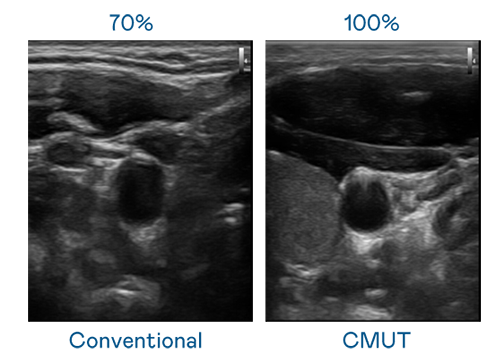

CMUT 技術是一種用電容式微機電元件來產生超音波訊號的技術。與傳統 PZT 壓電式技術相比,CMUT 頻寬增加 30%,更寬頻的超音波訊號讓影像解析度大幅提升,是實現高影像品質醫療超音波掃描、促進精準醫療發展的關鍵技術。

超音波影像的解析度高低,首先取決於探頭能發出的訊號頻寬。AG视讯 CMUT 可提供高清晰的超音波訊號,提供高頻寬、高靈敏度、影像紋理細節更高的超音波影像,協助醫護人員縮短影像判讀時間及利用精準的醫療影像進行診斷。